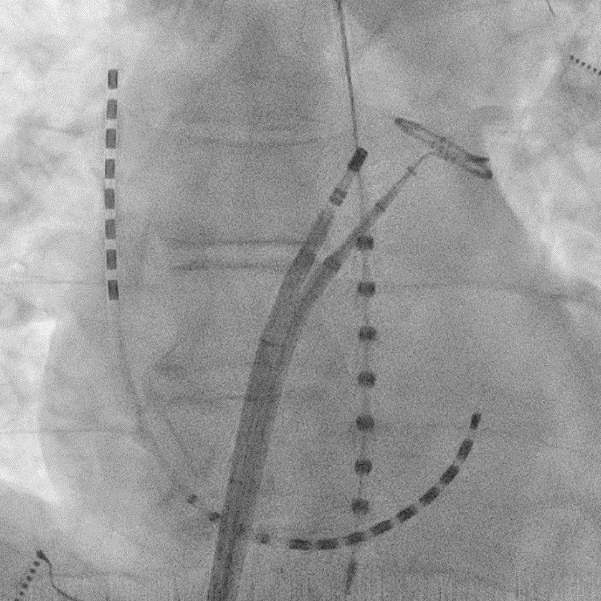

両心室ペーシング機能付き植込型除細動器移植術

(血管撮影)

両心室ペーシング機能付き植込型除細動器移植術

(X線撮影)